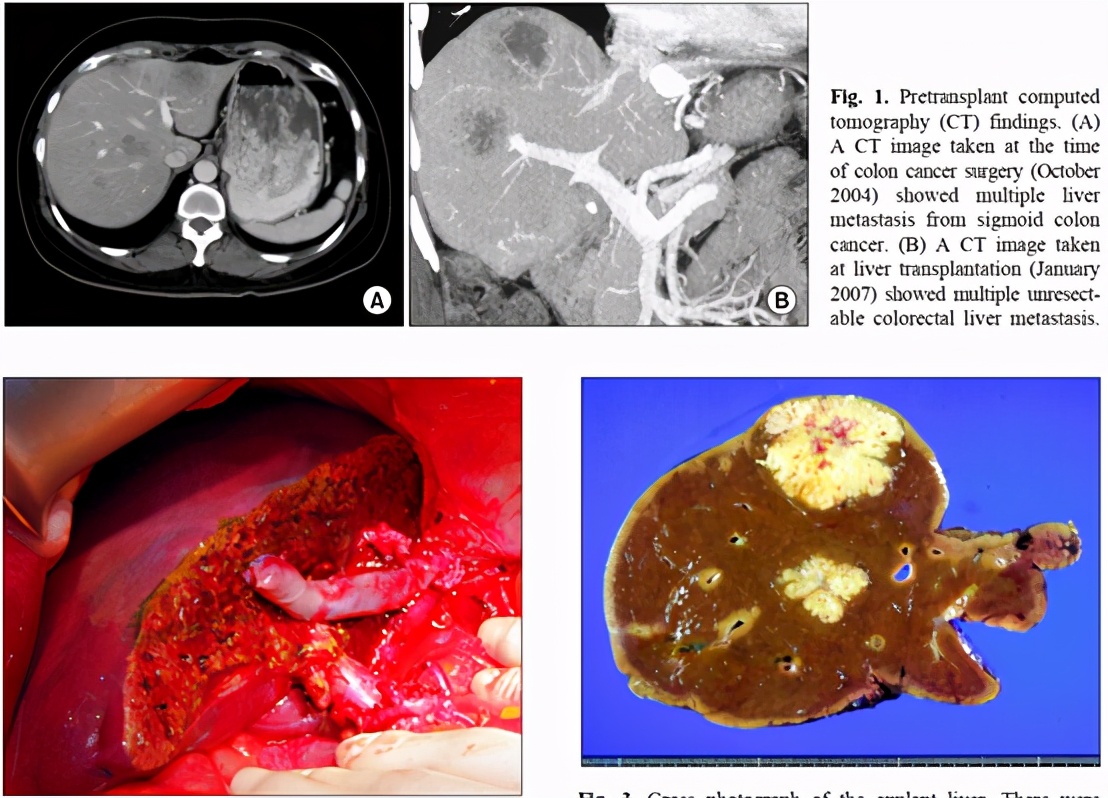

这是一例韩国女性病人。 2004年10月,当年49岁的这位女性病人在ASAN医学中心,被证实得了乙状结肠癌,同时发现多发性的肝脏转移灶,无法手术切除,陷入绝境。当时,她接受了肝动脉灌注化疗。经过七轮的治疗以后,肿瘤产生了一定的临床反应,肿瘤被部分抑制,但是并未完全根治。当时结肠肿瘤经手术获得切除,肝转移灶却一直存在,无法用手术或其它方法切除。后来病人由于肝脏的化疗副作用,发生了食道静脉曲张出血。病情危急。(病人没有乙型或丙型肝炎感染史)

在这种情况之下,病人接受了全面检查。评估了用肝移植治疗她的结肠癌肝转移的可能性。当时病人的所有病灶都局限于肝脏中。乙状结肠的手术部位,及身体其它部位都没有肿瘤的证据。当时CEA(癌胚抗原)的水平是220 ng/ml。

在没有其它现实的治疗方法面前,为了挽救她的生命,患者在2008年接受了活体肝移植,病人的姐姐为她捐献了部分肝脏,右半肝的活体肝移植手术非常顺利,术后曾经有过一次短暂出血,通过介入治疗获得解决。病人在移植之后,采用他克莫司进行免疫抑制治疗,至今已经随访了13年,都没有发现任何的病灶转移,达到了长期的存活。